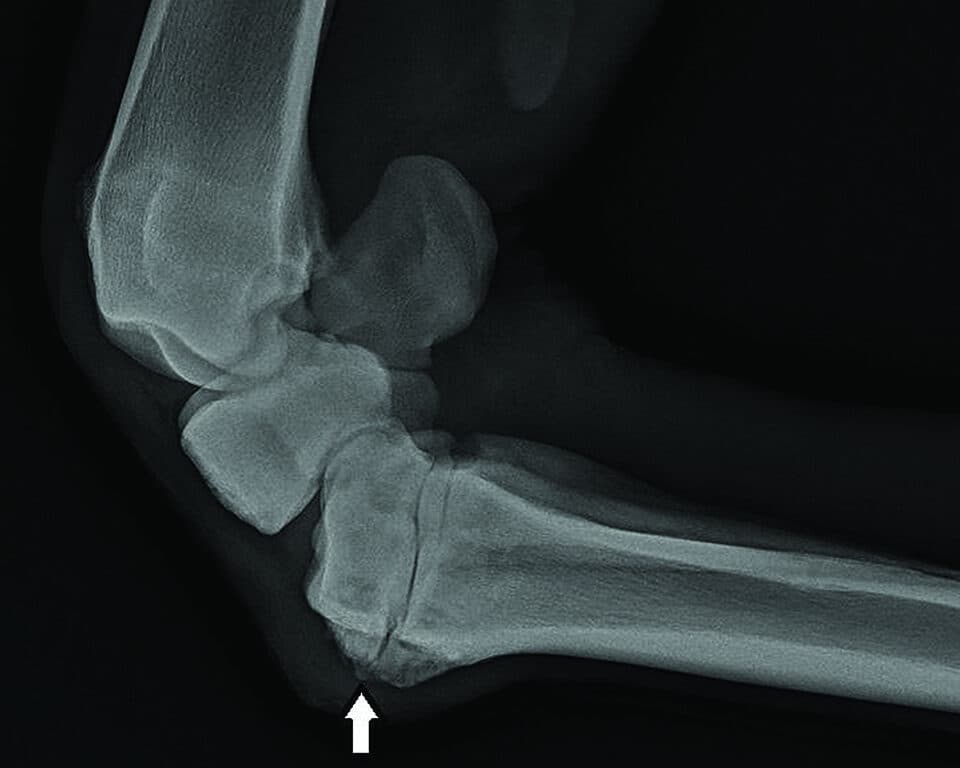

RESULTS: Researchers Verify Genetic Mutations for Osteochondrosis Risk in Horses

Osteochondrosis (OC) is a developmental orthopedic condition commonly diagnosed in young horses. The disease is caused by abnormal cartilage development resulting in the formation of lesions in joints, with the joints of the hind limbs most commonly affected. Osteochondrosis can be a mild to severe disease, but almost always requires surgical correction to prevent further joint damage. The disease results from a complex interplay of genetic and environmental factors. Attempts to influence the environment have had limited success in controlling the disease.

Understanding the genetics behind osteochondrosis represents the best chance for OC prevention. Some horse breeds, including Standardbreds, Warmbloods and Thoroughbreds, have a higher incidence of OC, emphasizing the genetic component of the disease. Researchers from the University of Illinois and the University of Minnesota identified several genetic mutations associated with OC in a population of yearling horses born and raised on a single breeding farm in the United States. To add statistical value to their findings, the team validated their data in a second, unrelated population of horses from Norway. The results of this study were a first step toward the team’s long-term goal of creating a genetic risk model for osteochondrosis that could be applied to individual horses.

Defining the genetic and biomechanical factors in OC development will improve early intervention to help reduce the risk of clinical disease in individual horses and high-risk breeds. The new information gained from these investigations will help guide management changes and also aid in informed breeding decisions to reduce disease incidence in horses.